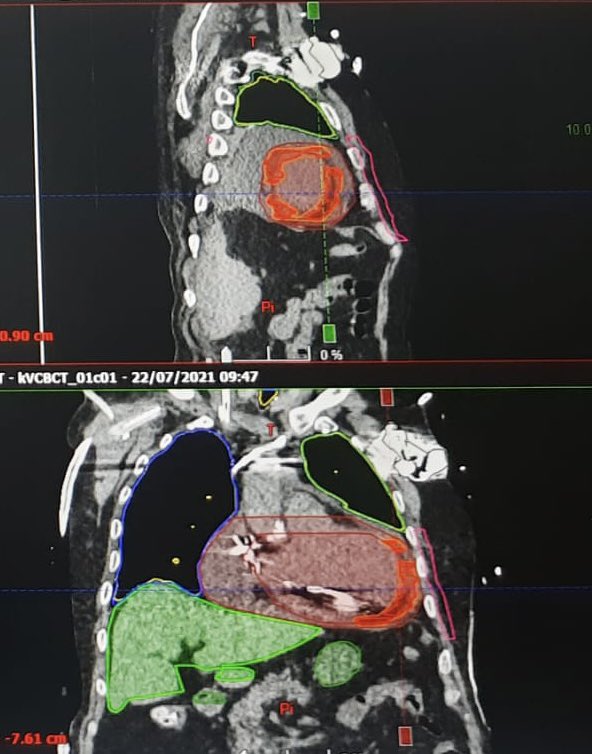

Our first noninvasive VT radioablation case. Who would have ever thought to perform a VT ablation in 6 min. Thanks @DoctorPhillEP for leading the way and @JeffTheEp for the advices. #RadiateVT #EPeeps #AblateVT @SilviaMagnani6